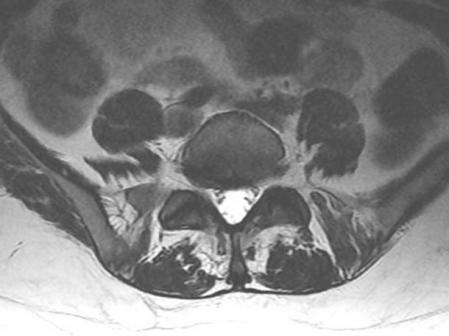

Imagen de una caso de artrosis facetaria

"Su diagnóstico, además de clínico, con la certificación de los síntomas, se confirma con la realización de pruebas de imagen como la resonancia magnética lumbar, que pone de manifiesto la localización exacta de la degeneración del cartílago facetario", agrega el doctor Moya.